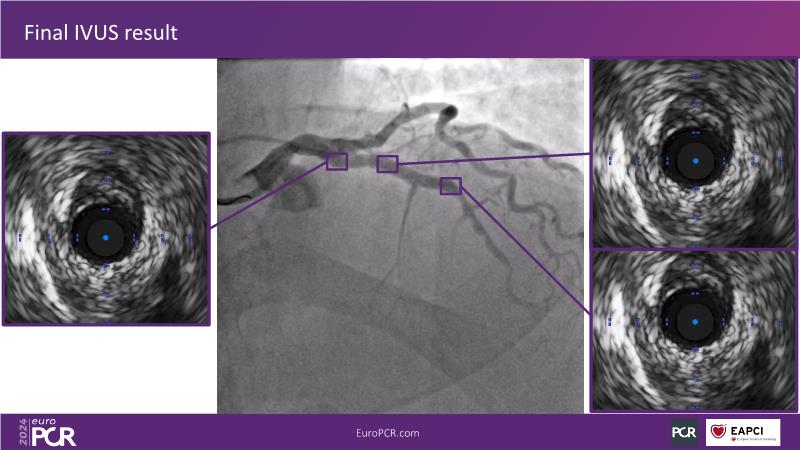

Explore this session to uncover the common association between calcium and acute coronary syndrome, and how intravascular lithotripsy (IVL) offers a safe solution for calcified lesions, with comparable procedural success rates. However, note that ACS cases involving calcium may lead to higher major adverse cardiac events (MACE). Special attention is warranted for women due to their propensity for adverse outcomes. Discover how the C2 + IVL catheter enhances procedural flexibility, yet high intracoronary imaging rates did not yield differences in MACE. Additionally, learn about the potential role of IVL in treating in-stent restenosis (ISR).

- To share clinical experience to uncover practical tips and techniques for intravascular lithotripsy in complex calcified lesions